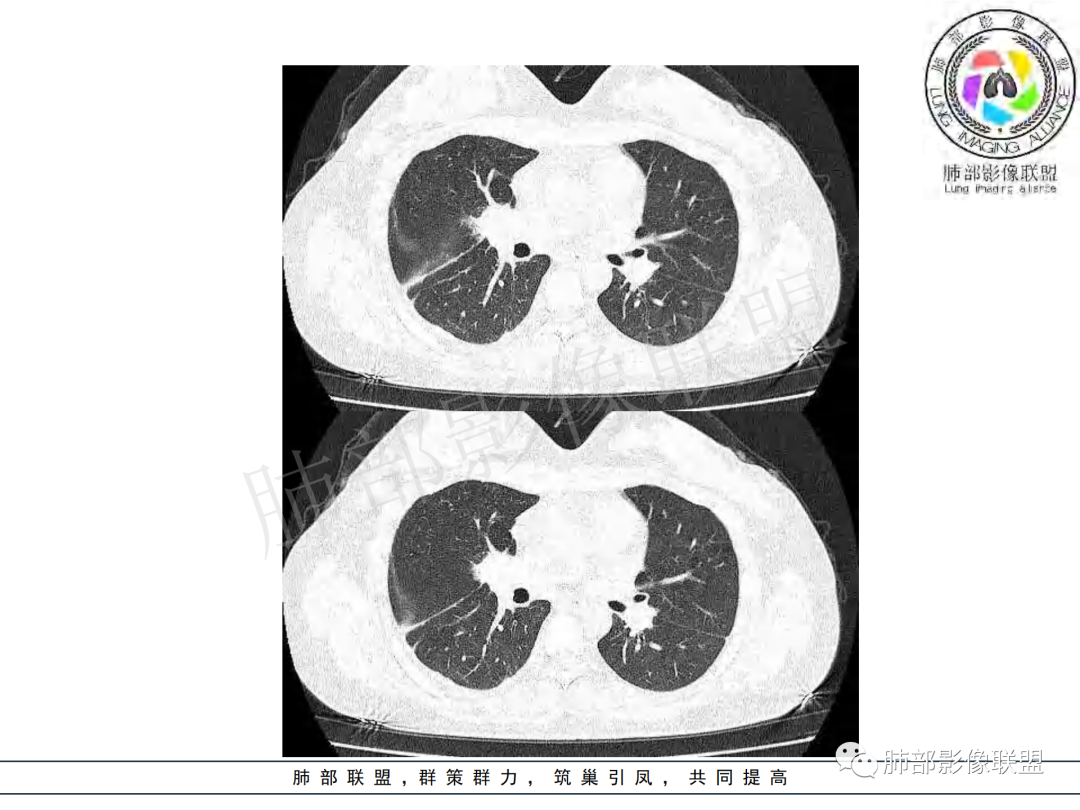

右肺肺门旁肿块,右肺中间段支气管腔内结节,增强强化不均;纵隔多发淋巴结环形强化,右侧少量胸腔积液,临床发热入院,考虑结核,鉴别肿瘤。

右肺门增大,远端花花草草不明显,支气管管壁增厚,纵隔淋巴结环形强化,年龄,病程,考虑炎性病变,结核可能,有个层面支气管截断,有强化,鉴别粘表。

纵隔多组及右侧肺门多发肿大淋巴结,部分融合,不均匀强化,内见斑片状坏死区及环状强化,后者坏死边界尚清晰,肺门区肿大淋巴结与肺组织边界不清,年轻女性,8个月病史,发热首发症状,考虑淋巴结核并向肺内侵及(破溃?),鉴别淋巴瘤

女,20,病程长达8月,发热、胸痛、右侧胸腔积液病史。胸部CT:右肺门旁不规则肿块影,右中间支气管腔内结节,纵隔多发淋巴结肿大;强化不均匀,灶性坏死灶,环形强化;右侧少量胸腔积液并局部肉芽肿样突起。年轻女性,长病程,多部位,考虑慢性炎症,结核?鉴别肿瘤。

青年,右肺门增大,见软组织肿块影,部分支气管腔结节,并管腔狭窄,增强后明显不均匀强化,伴纵隔多发肿大淋巴结,环形强化,考虑恶性,类癌,鉴别支气管内膜结核

右肺门不规则肿块,向气管腔内生长,不均匀强化,其内粘液栓,纵隔淋巴结增大,部分有坏死,胸膜结节强化,考虑恶性,粘表?类癌?鉴别结核

右肺肺门旁肿块,右肺中间段支气管腔内结节,增强强化不均;纵隔多发淋巴结环形强化,右侧少量胸腔积液,考虑结核可能,鉴别肿瘤。

年轻女性,慢性病程,发热、胸痛。右肺门旁不规则肿块影,纵隔多发淋巴结肿大;强化不均匀,环形强化;右侧少量胸腔积液;首先考虑结核,鉴别肿瘤,结节病。

右肺门及纵膈多发淋巴结肿大,部分融合,密度不均,部分呈环形强化,年轻女性,病史长,发热,考虑淋巴结结核

年龄和病史比较符合结核,但是中叶支气管好像堵塞了,管腔有新生物,恶性肿瘤也不能排除,做一个支气管镜应该能确诊

年轻女性 大支气管占位恶性三件套 高强化 内部可见无强化区,无强化区与强化区内边界大部分不清晰,类癌、粘表、腺样囊性癌。首先考虑粘表   其次需要鉴别的有结核   这么大片的坏死 结节病可能性小

慢性病程,前纵隔右肺门旁多发淋巴结肿大;强化不均匀,环形强化;右侧少量胸腔积液;考虑结核,鉴别结节病。

年轻女性,右肺门区病变伴纵隔淋巴结肿大,强化显示环形强化,考虑结核可能性大

年轻女性,右侧肺门一肿块,边缘不规则,纵膈淋巴结肿大,环形强化,右侧胸膜少量积液,发热首先考虑结核鉴别恶性淋巴瘤

支气管腔内有占位,肺门区病灶和胸膜结节明显强化,淋巴结环状强化为主,部分明显强化,年轻女性,首先考虑结核,鉴别腺癌

青年女性,发热、胸痛、右侧胸腔积液病史,病程8个月。曾多次抗炎后均有好转。CT:右肺门旁肿块影,双侧胸膜结节,纵隔多发淋巴结肿大,边缘模糊;增强渐进性明显强化,纵膈淋巴结较彻底坏死灶,边缘环形强化。考虑结核,鉴别恶性肿瘤。

女性,20岁。高热、畏寒。右肺上叶近肺门区不规则肿块,周围斑点、片小结节影伴肿大淋巴结,肿块包绕并突入右主支气管腔内,增强后肿块不均匀强化,淋巴结环形强化中心低密度,考虑结核。

纵隔肺门及两侧胸膜强化结节,支气管管腔不通畅。结核能解释临床及影像,就是强化有点猛,这个妖怪真不好说。恶性如类癌/高级别黏表/恶性间皮也要考虑。

本例患者,年轻女性,慢性病程,多次抗感染治疗效果不佳,实验室检查示白细胞及中性粒细胞不高,不支持普通细菌感染,虽然肺泡灌洗液X-Pert检测阴性,结合患者胸部CT结核感染亦不能排除,胸部CT主要表现为右侧肺门及纵隔淋巴结肿大,仔细观察不难发现右中间支气管内新生物凸向管腔内,增强扫描,右肺门(10R)及纵隔淋巴结(2R,4R)明显不均匀强化,内部呈不规则低密度无强化区,被周边高强化区包绕(环形强化)的特点,首先应当想到纵隔淋巴结结核诊断。淋巴结分布亦不符合肺部恶性肿瘤迁徙途径。